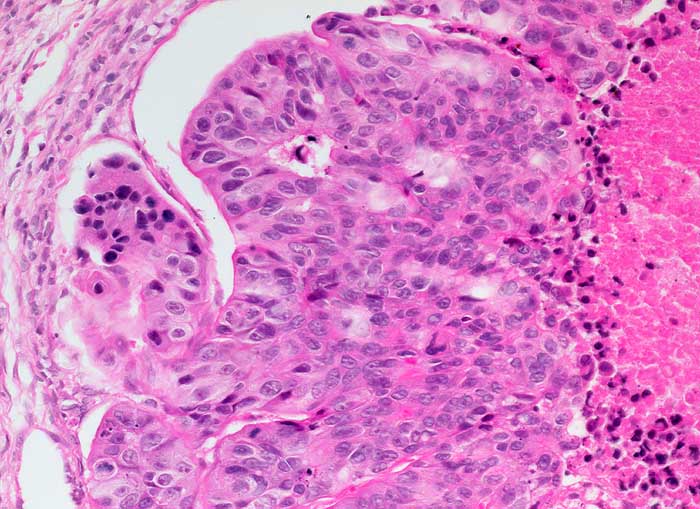

PathoPic ID 6396 - Kolonkarzinom: Metastase

Kolonkarzinom: Metastase

maligner Tumor

Portio

Genitalorgane, weiblich

Infiltrate eines soliden Adenokarzinoms mit ausgedehnten komedoartigen Nekrosen gut passend zu Metastasen eines Kolonkarzinoms.

Kolonkarzinom. Postmenopausale Blutung.

Histologie

200